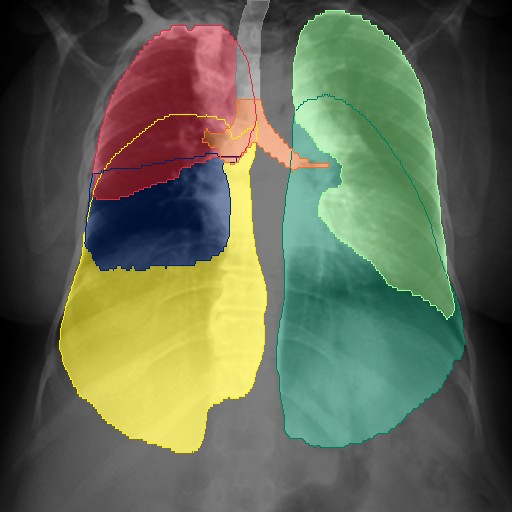

We show qualitative results for frontal projections in Fig. 2. We show a subset of classes belonging to the supercategories lungs, vascular systems, bones, and abdomen/digestive system. The predictions show minor deviations at the boundaries of the individual classes of the respiratory and vasculature system, while some inaccuracies become visible in the abdominal area. The qualitative results for the lateral projections are displayed in Fig. 2. Akin to the frontal view, the predictions show smoother borders but align with the ground truth. Apart from this, the segmentations provide matching insights on the thoracic anatomy with a slight deviation from the ground truth for both frontal and lateral views.

Fig. 2 shows quantitative segmentation results for frontal (top row) and lateral (bottom row) views. We display the class performances in the form of IoU (left), DICE (center), and Hausdorff distance (right) for each sample as a scatter plot with the mean performance for the classes shown by a line plot. Generally, we see performances for standard spinal classes, such as the thoracic vertebrae with average IoU-scores above 80%, while the average performance of rare vertebrae of the dataset belonging to the cervical and lumbar spine can drop down to 40%. In the frontal view, there exists more variance in thoracic vertebrae segmentation performance compared to the lateral view. Bone structures such as the sternum, clavicles, and scapula achieve IoUs in the mean from 85% to 95%. For ribs, we can see a noticeable performance drop for the anterior parts of the lower ribs independent of the side. The lower anterior ribs typically do not contain a large area, making them difficult to segment. This behavior is mirrored in the lateral view across the metrics. Abdominal classes can vary in segmentation quality as they occur in a nearly homogenous region. For example, while the liver or stomach are typically well-segmented, the duodenum and kidneys are more complex. Heart and Lung related classes show near-perfect segmentations with scores above 90% IoU. Breast tissue segmentation in comparison only achieves a mean of 70% mIoU. It can be noted that classes in the lateral view tend to have slightly better scores than their frontal counterparts.